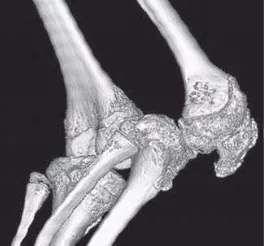

При прогрессировании заболевания возможно развитие значительного сужения суставных щелей и анкилозов в периферических суставах (фото 14).

![]() | ![]() | ![]() |

Фото 14. Анкилоз коленного сустава при ЮАС. КТ: 3D-реконструкция [4].